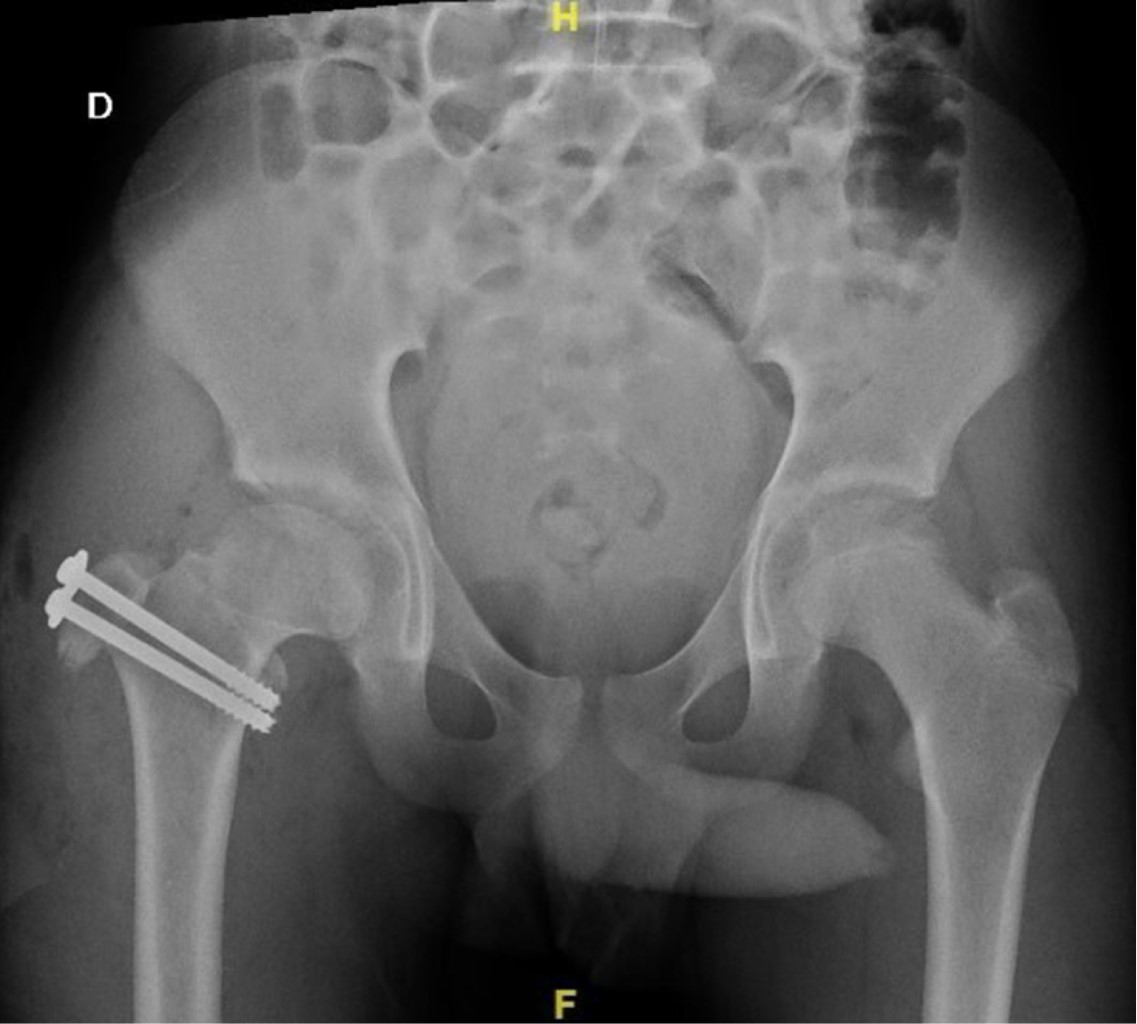

Treatment of femoroacetabular impingement with controlled dislocation of the hip

The femoroacetabular impingement is a syndrome caused by abnormal contact between the femoral head and the acetabulum; it can progress in complications, and the treatment must be individualized with the aim to restore the functionality of the joint. A case of a 12 years old patient who presented clinical findings about impingement, he has history Perthes disease. We performed a surgical hip dislocation technique with femoroplasty. We obtained good results. The clinical and radiographic characteristics of the patient has described and the case resolution.

Figure 3